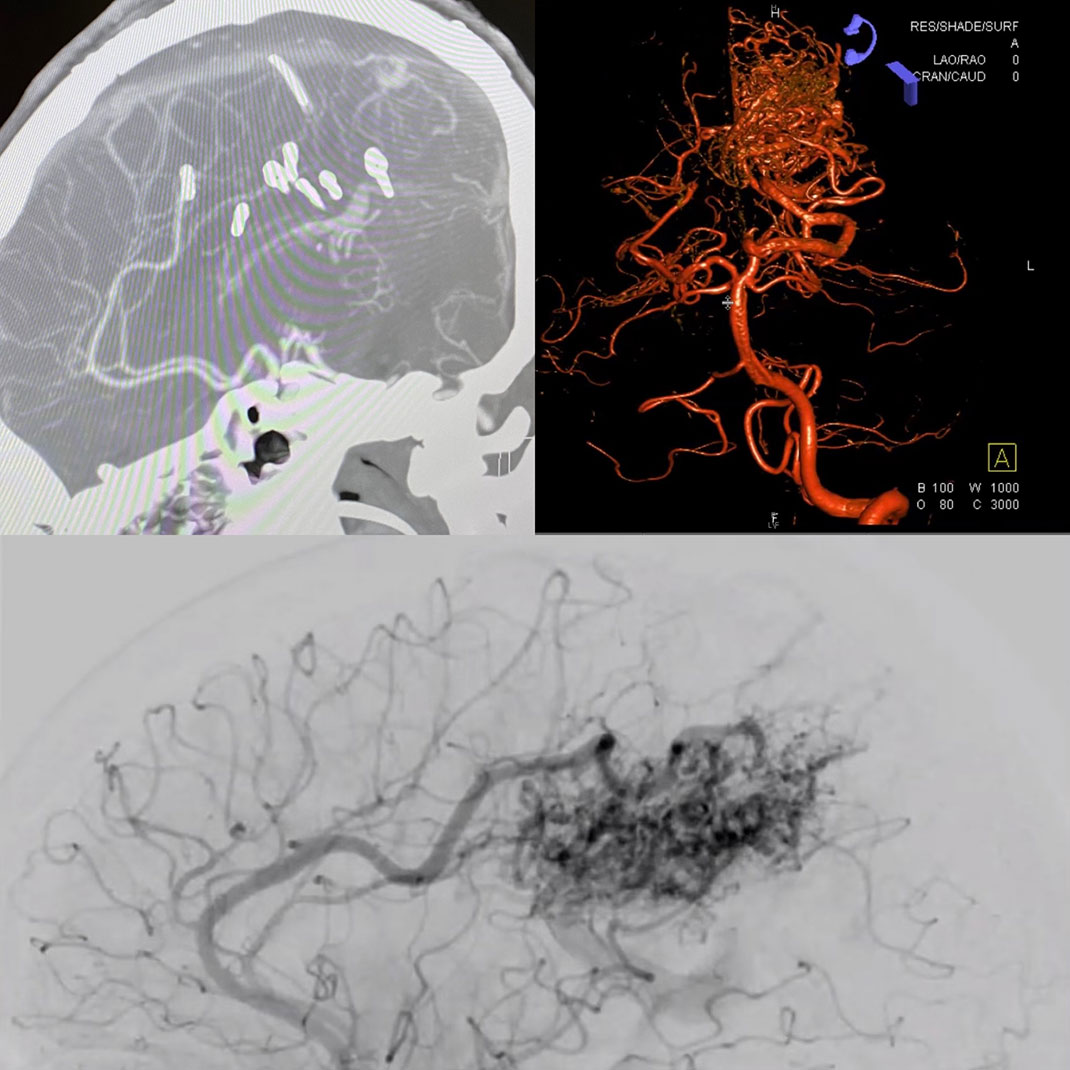

Brain scans showing AVM formations.

Scans showing the AVM formations in Jenn’s brain.